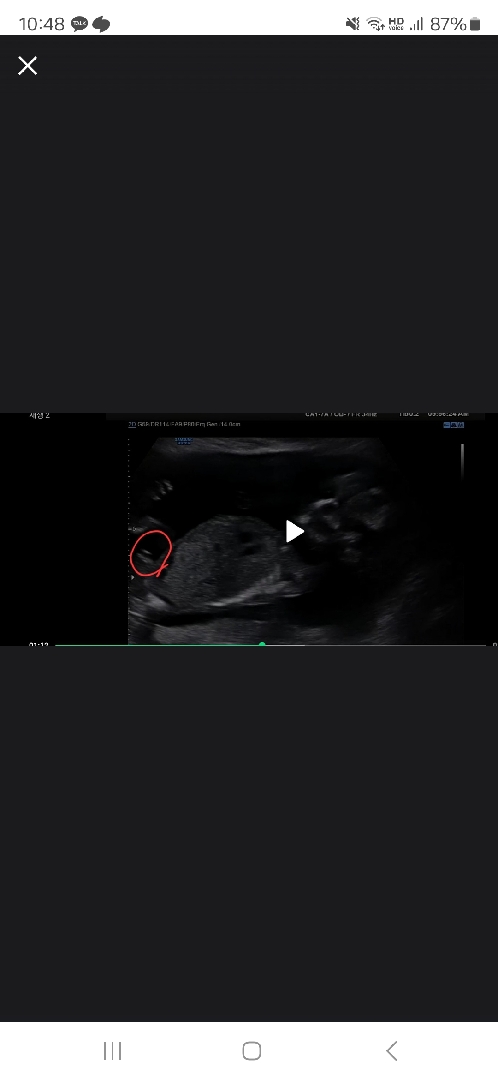

혹시 아들일까요?

체크한부분을 보면 아들이겠죠?

각도보니까 아들 맞는거같아요

저는 저부분은 허벅지같기도해용 .. ㅇ_ㅇ